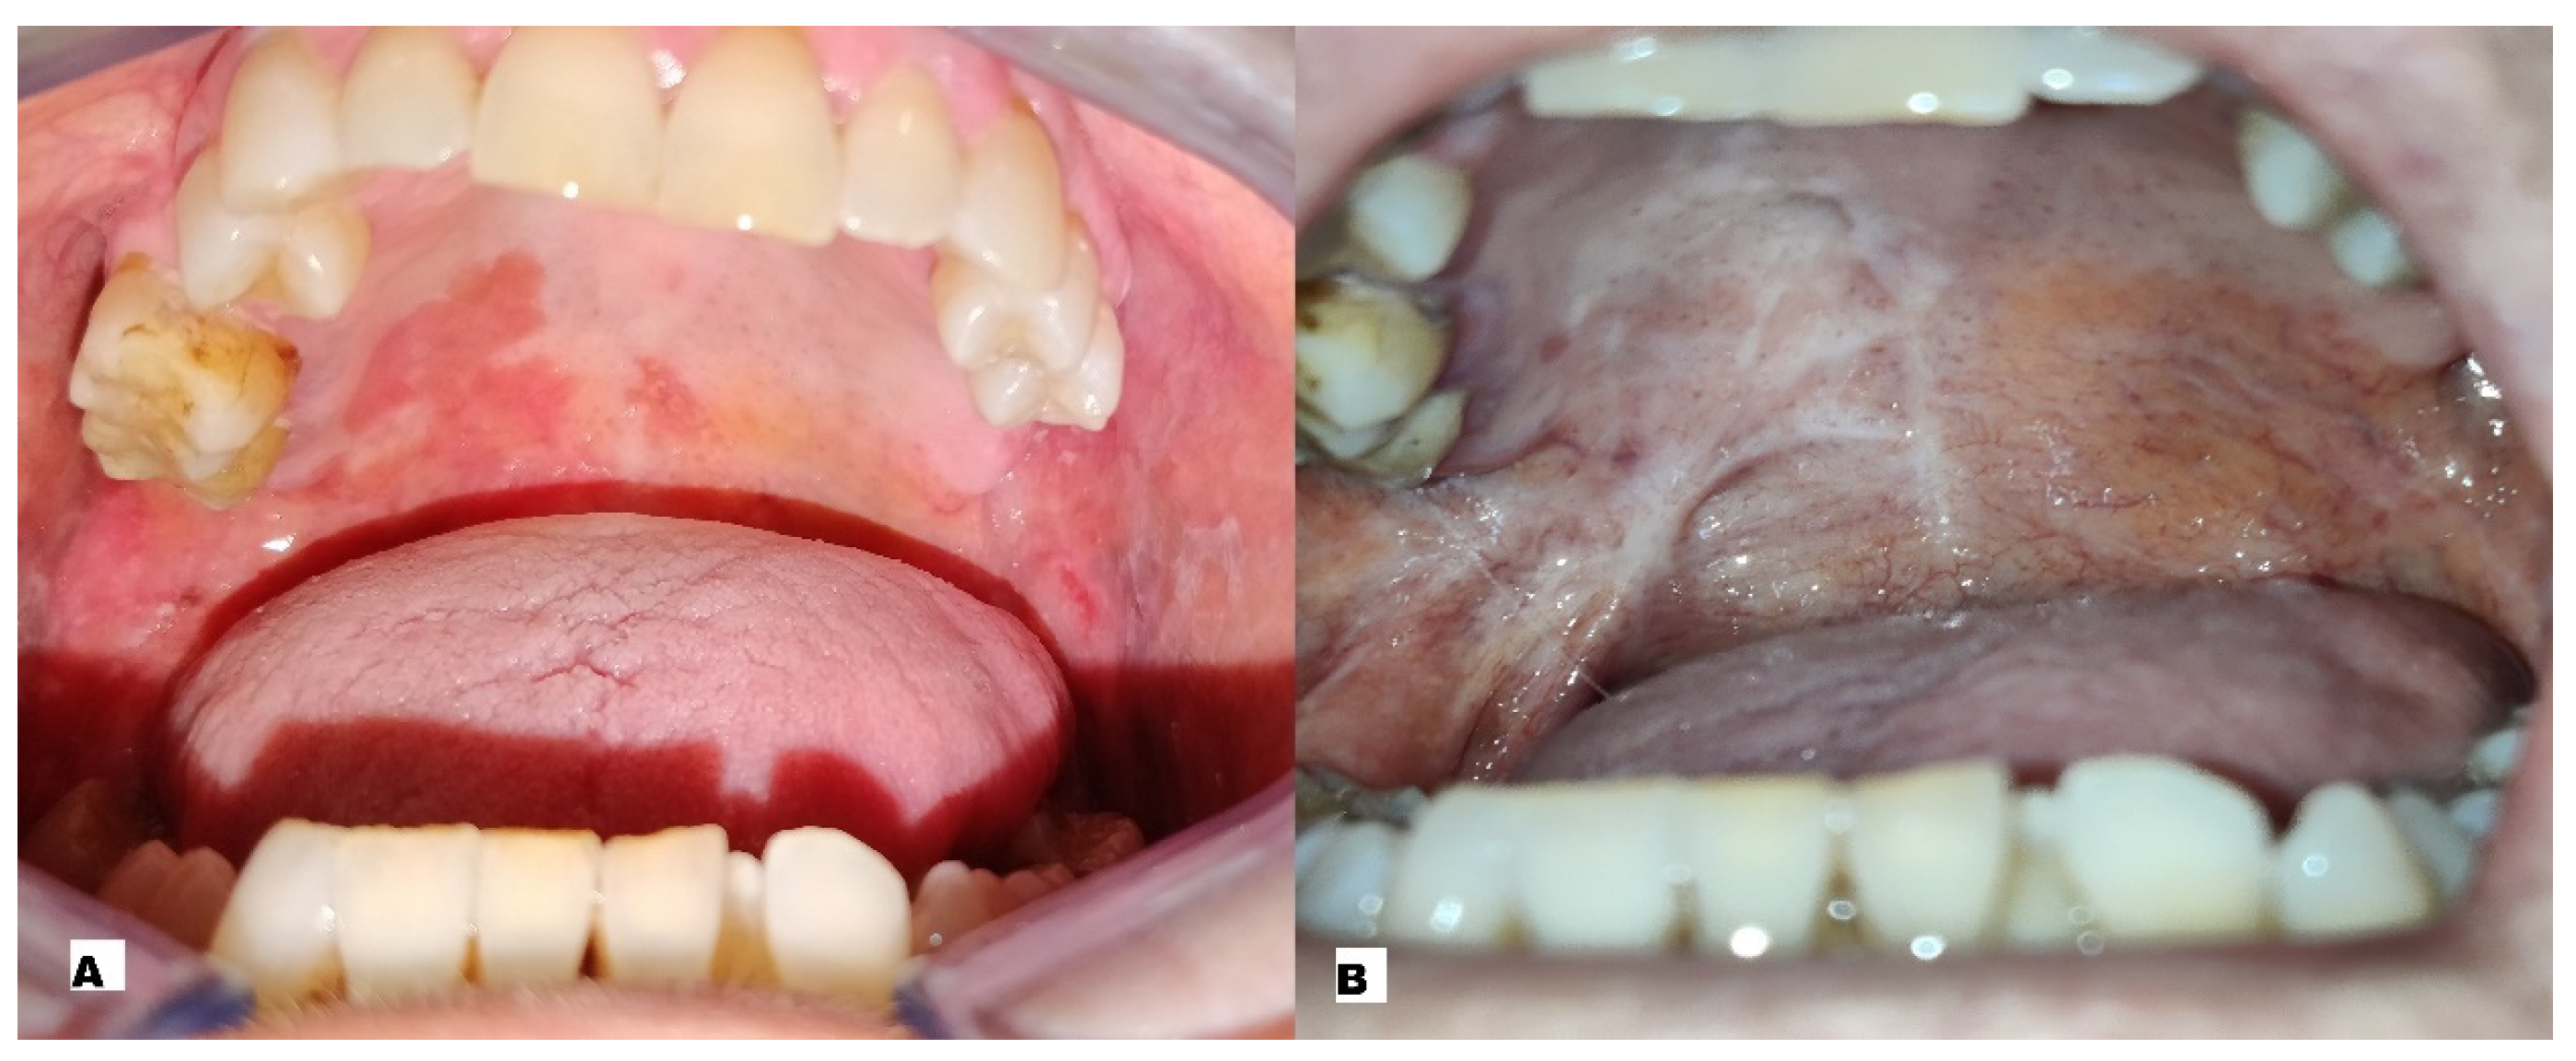

| 3 | M | 71 | Strong smokers | Strong drinker | G2 | Buccal mucosa | T3N0 | 1 ECT session |

| 5 | F | 76 | Moderate smoker | Moderate drinker | G3 | Buccal Mucosa | T3N0 | 3 ECT sessions |